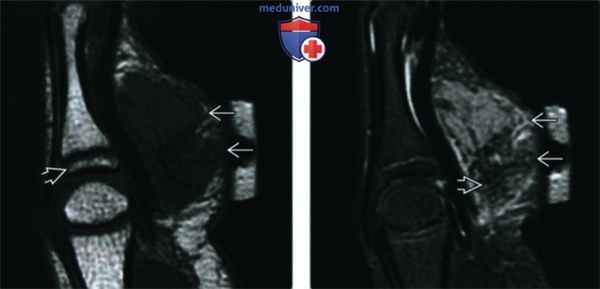

Рентгенограмма, МРТ при кальцифицирующейся апоневротической фиброме

б) Визуализация:

1. Общая характеристика:

• Лучший диагностический критерий:

о Небольшая опухоль в области ладони или стопы у ребенка

• Локализация:

о Ладони, подошвы, запястья и голеностоп:

- Редко встречается в спине, плечах, нижних конечностях, шее и брюшной стенке

о В области сухожилий, фасций и апоневрозов

• Размер:

о Обычно • Морфология:

о Солитарное образование, характеризующееся нечетким контуром

о МРТ для определения размера и локализации опухоли

4. МРТ при кальцифицирующейся апоневротической фиброме:

• Гипоинтенсивные на Т1 ВИ и Т2 ВИ зоны

• Интенсивное контрастирование гетерогенного характера